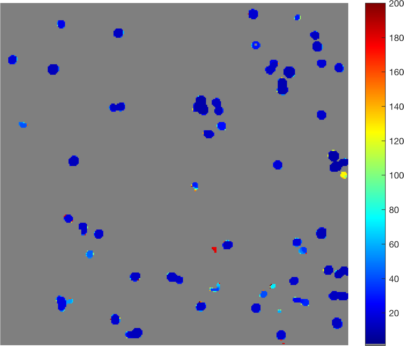

5.4 Fluorescence microscopy images containing Circulating Tumor Cells

In this subsection we demonstrate how our multiscale segmentation approach can be applied to the analysis of Circulating Tumor Cells (CTCs). Before presenting some experimental data sets we will first give a short introduction on CTCs, associated research questions and challenges for diagnosis and treatment of cancer patients.

Circulating Tumor Cells are cells that dissociate from a primary tumor and invade the blood stream. In recent literature it was shown that the number of CTCs present in the blood is associated with the survival chance of a patient and can be used to guide therapy of cancer patients. The elimination of CTCs indicates effective therapy whereas increase or failure to eliminate indicates a futile therapy. A challenge in the identification of CTCs is that they are very rare and therefore difficult to detect among other cells in the pool of blood cells. The gold standard for CTC enumeration is the CellSearch system and in prospective multicenter studies a threshold of 5 CTCs / 7.5 ml of blood was used to separate patients with metastatic disease into those with favorable and unfavorable prognosis [CBE+04, dBSM+08]. Currently all known CTC analysis tools are based on subjective morphological criteria and objects can be classified differently by different operators which results in different interpretation of the status of the patients. The low cell counts and subsequent statistical analyses further increases the chances of mistakes. The problem of subjectivity in the CTC analysis is currently addressed by the development of an open-source toolbox to automatically detect and classify CTCs in datasets from various machines and institutes. This project is part of a European consortium called CANCER-ID that aims at validating blood-based biomarkers and is funded by the European Union. One key component of this toolbox is the development of a (nearly) parameter-free segmentation algorithm which performs reliably and efficiently on multiple tumor cell datasets (see Figure 14).

Moreover, in recent studies [CDA+10] it was hypothesized that not only the definition used to classify objects as CTC predicted clinical outcome but also those objects that did not match the criteria of an intact cell. A schematic overview of different cell classes and their relative frequencies is shown in Figure 13. Here, green is a fluorescence marker indicating the presence of cytokeratin expressed in cancer cells but not on white blood cells and magenta is a fluorescence marker indicating the presence of DNA thus showing the nucleus of the cell. When comparing the green marker among the different CTC classes we observe that the signal clusters strongly vary in size (area) and therefore motivate the usage of our multiscale segmentation approach.

In Figure 14 (a), (d), (g) and (j) experimental data sets are shown. From the original image sets, consisting of three different fluorescent color channels, we extracted the tumor cell marker (green) and used those images as input for our multiscale segmentation approach. Although the difficulties vary between all images (inhomogeneous background, noise, cell clusters, mixture of size and intensity scales), we can process all images with our multiscale segmentation approach with the exact same parameters. This is essential for the development of a user-friendly (parameter-free) toolbox for CTC analysis. Note that the dim spots in image (d) are not cells but only pores of a filter used to collect cells (bright spots) and therefore it is not desired to segment them. The resulting spectral response functions for all four images are shown in Figure 14 (b), (e), (h) and (k) with a color coding corresponding to the coding used in the segmentation results in (c), (f), (i) and (l). The color coding of the response function shows that all objects which appear later in our segmentation and therefore belong to finer scales have a yellow to reddish color in the color-coded segmentation. The very large and intact cells are blue (with some small artifacts at the boundary) and smaller cells (or large fragments) are shown in light blue to green. We can nicely observe that the object colors cover the whole color scale range. For images that are more complex (e.g. (d) and (j)) also the spectral response function is more complex but the color-coded segmentation shows that nearly every object appears in one step and thereby has a clearly defined scale that we use as a feature in our classification approach. Here, we profit from the fact that not only Wulff shapes (perfectly circular objects) but also other eigenshapes appear in one step in our segmentation. Hence, this segmentation approach not only provides all contours automatically without any parameter adaptations but simultaneously also a simple classification of cells based on their size (scale resp. color/appearance time). This analysis can be applied to all color channels separately and be used together with more features in a subsequent automatic classification approach. The constants and can again simply be estimated a-priori from the data by a simple thresholding and averaging approach and are fixed throughout the iterative process.